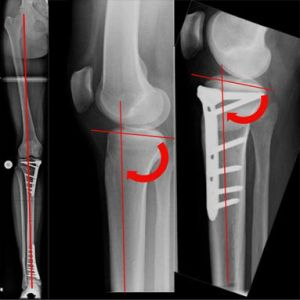

Individualisierte Vorgehensweise beim O-Bein (Bild 4). Infolge einer Verletzung der kniegelenksnahen, innenseitigen Wachstumsfuge resultierte dort eine diskrete Beinverkürzung mit O-Beinfehlstellung. Durch das aufklappende Verfahren wurden sowohl Beinlänge wie –achse ausgeglichen.